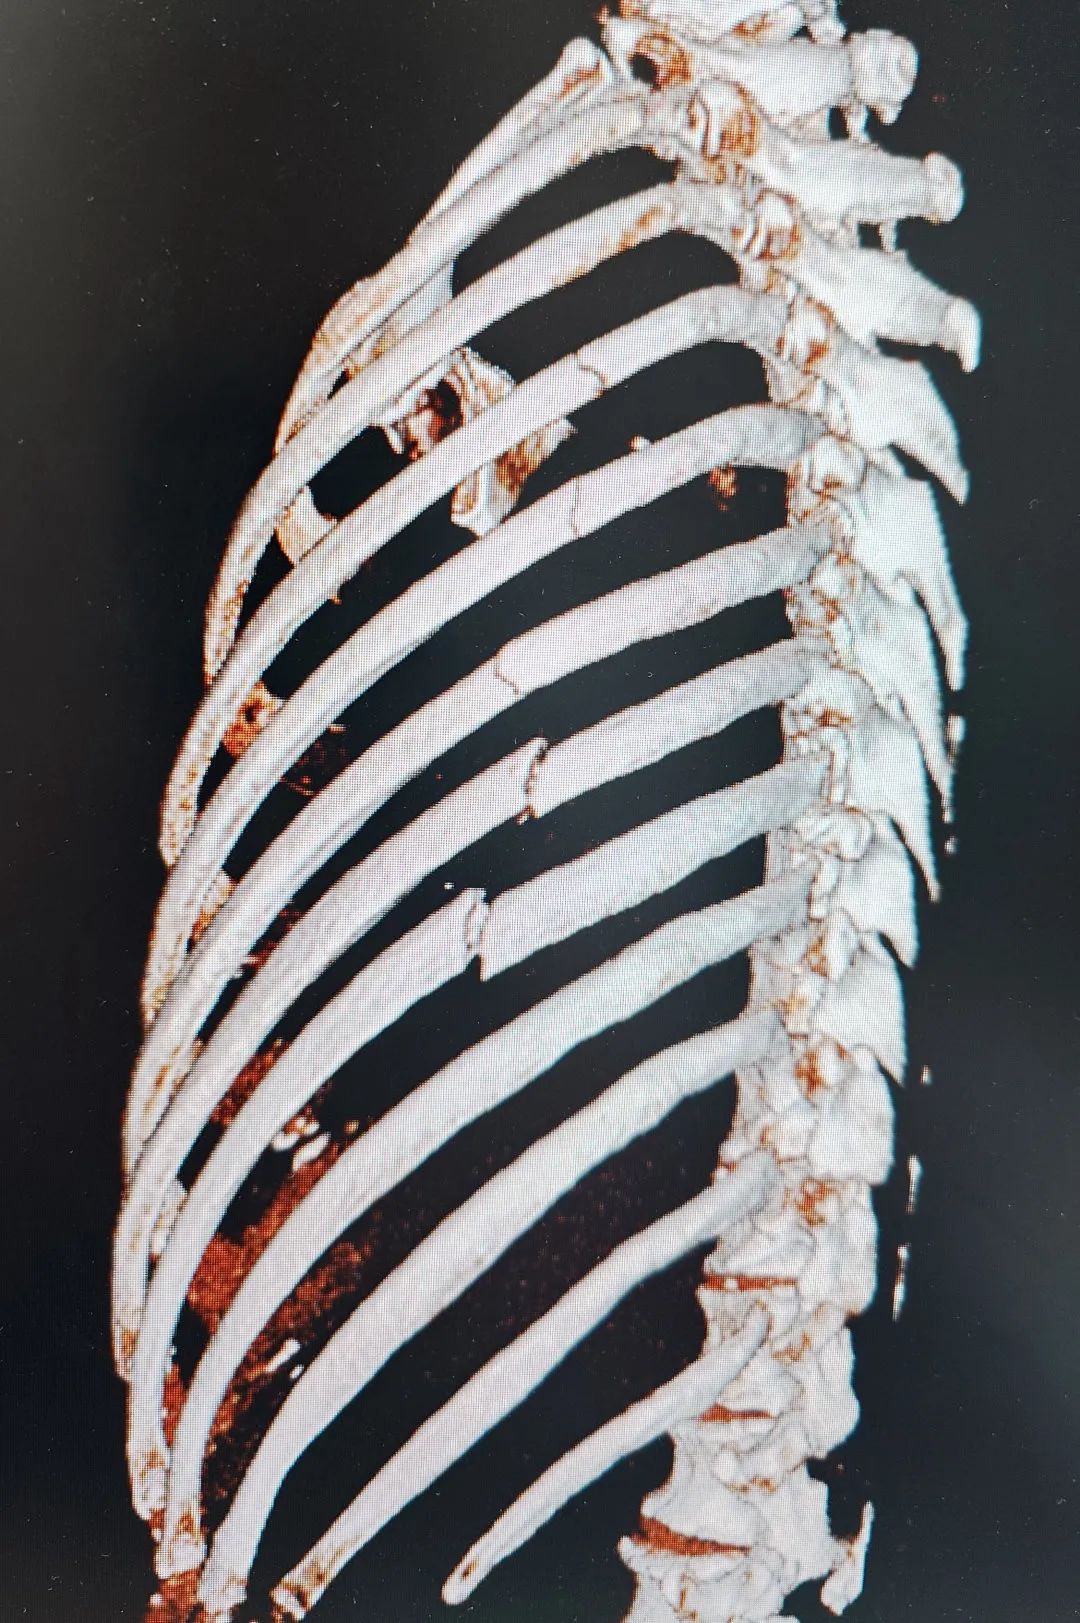

【技术领航】72岁老人摔断6根肋骨命悬一线!市二院胸外科孙振教授团队助其快速重生!

夕阳西下,本该是悠闲归家的时刻,对72岁的李大爷来说却成了惊魂瞬间。下午4点,他像往常一样骑着自行车,不料途中突发意外,连人带车重重摔倒在地!剧痛瞬间从左胸蔓延开来,李大爷面色痛苦,不仅无法动弹,胸闷、气促的感觉更让他喘不过气,120紧急将他送至葫芦岛市第二人民医院急诊科。